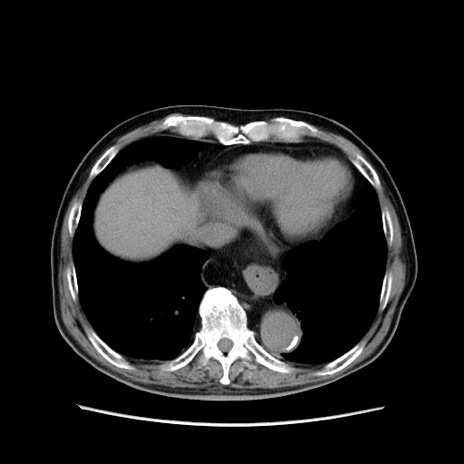

【症例】80歳代男性

【主訴】左側腹部痛、嘔吐

【現病歴】本日早朝より左腹部に痛みあり。昼頃嘔吐認めたため、救急要請。

【既往歴】直腸癌(Mile手術)、胆摘

【身体所見】意識清明、BT 35.9℃、BP 221/93mmHg、SpO2 97%(RA) 、腹部:左ストーマ周囲に限局性の腹部膨隆あり。 膨隆部自発痛・圧痛あり・軟。

【データ】WBC 7700、CRP 0.09